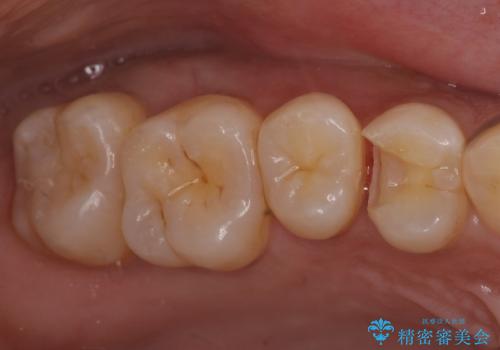

3. 奥歯の虫歯 セラミックインレーで治療の治療後